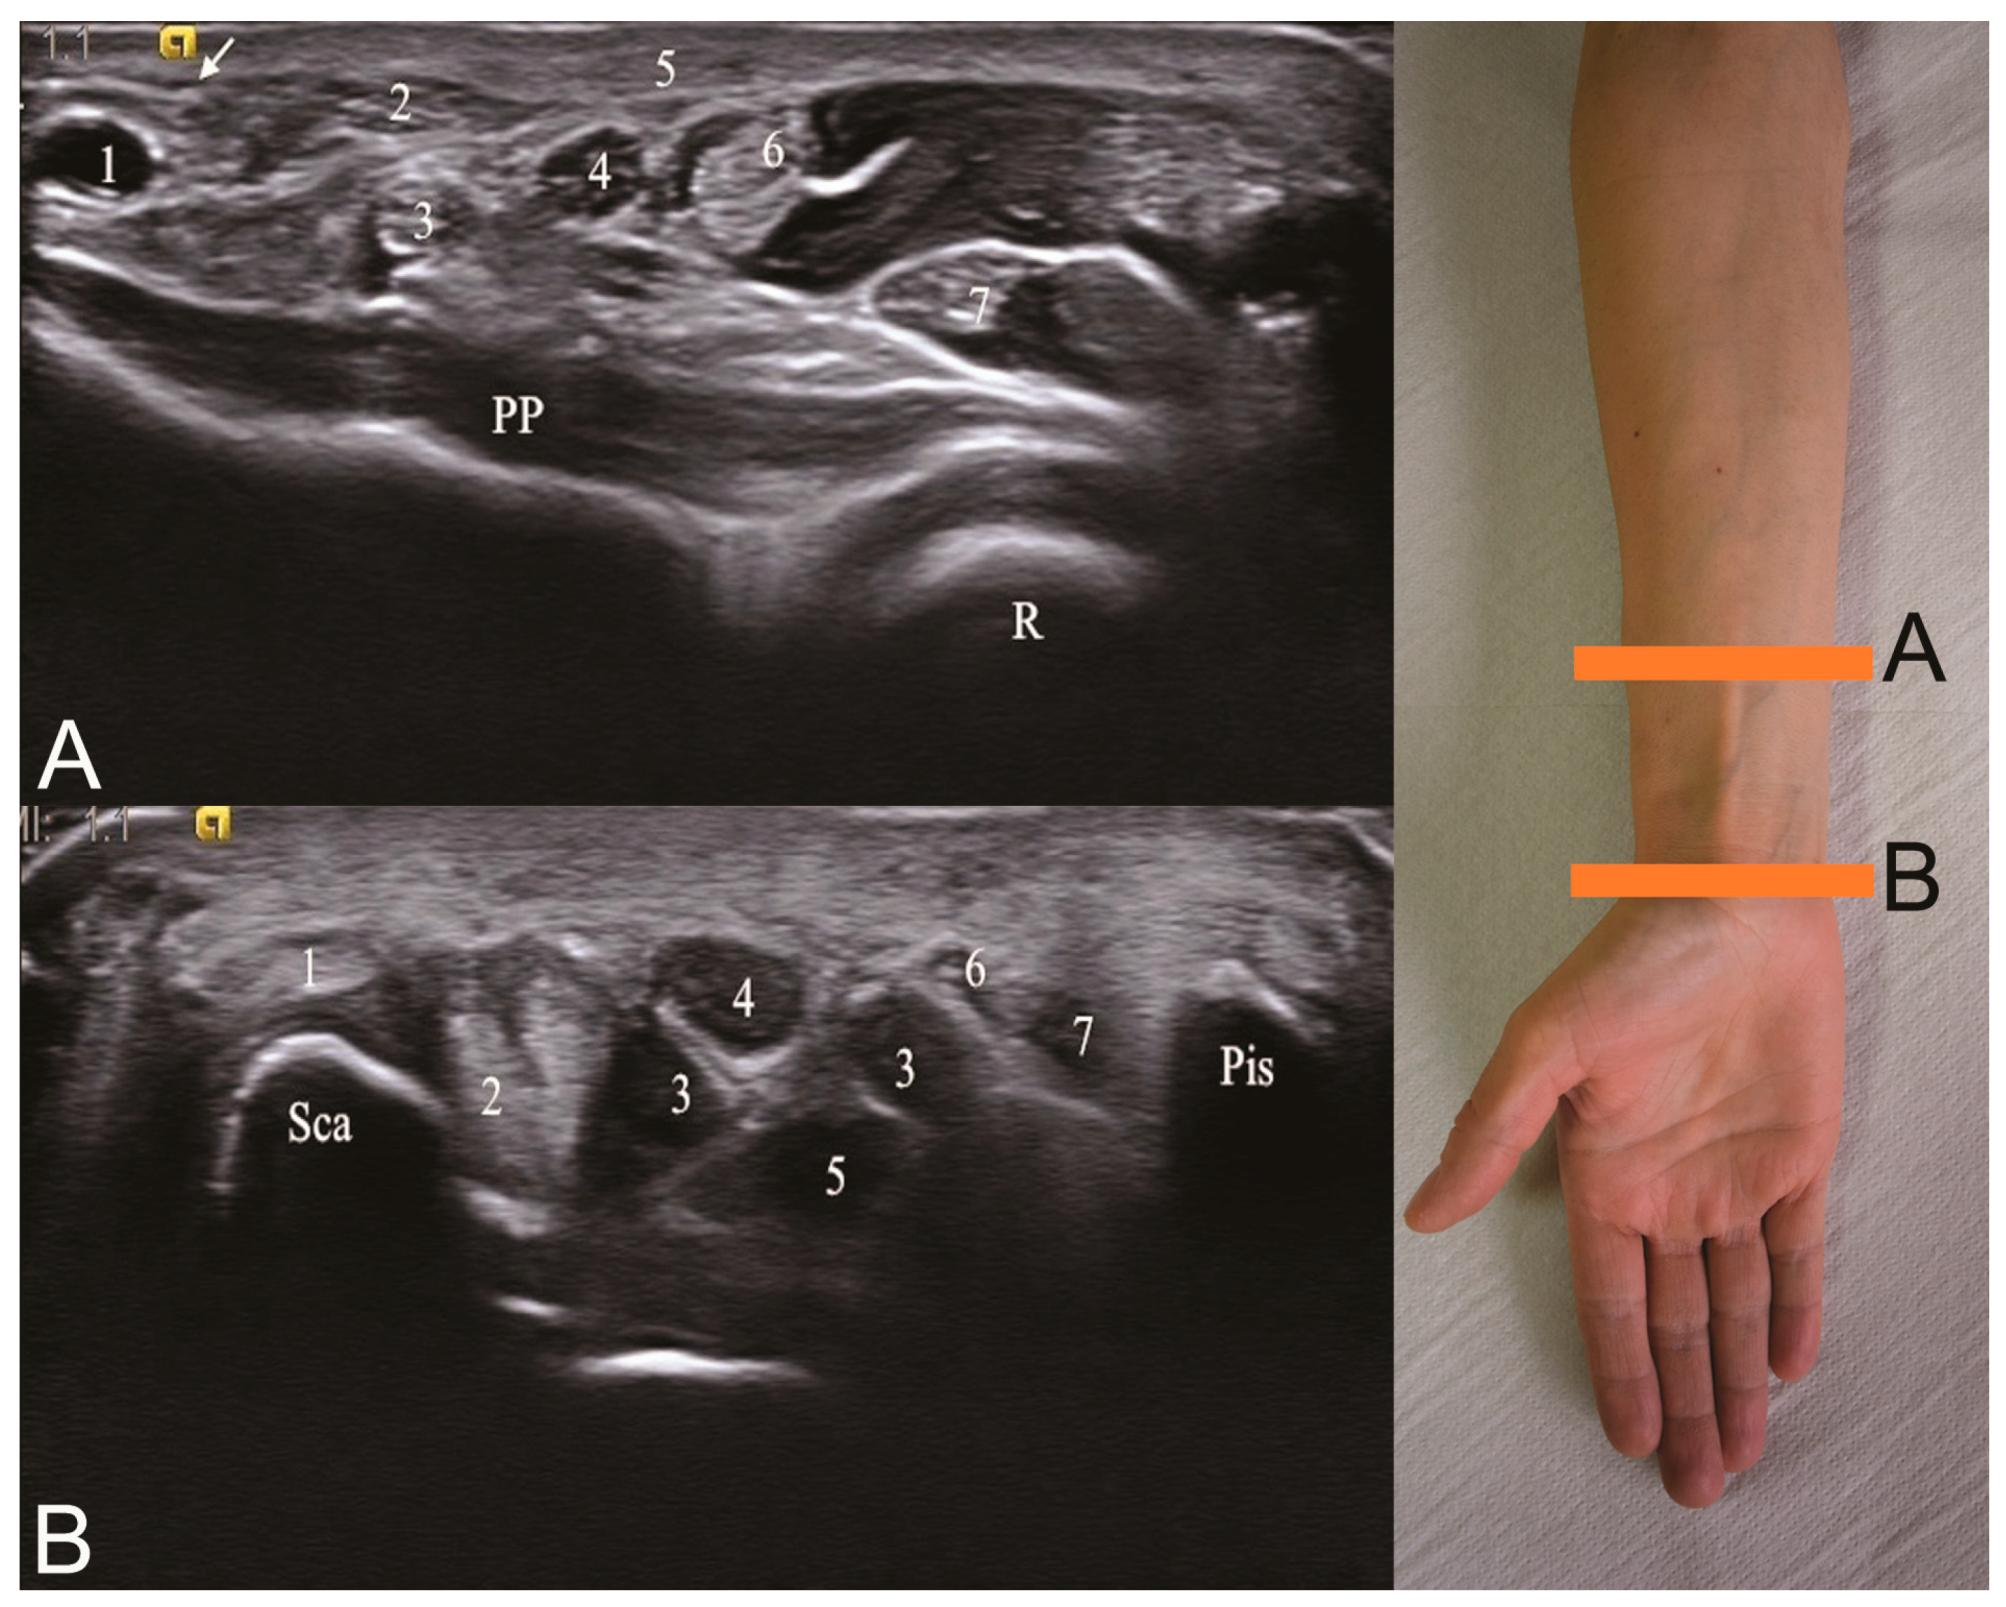

2.3. Ultrasonography